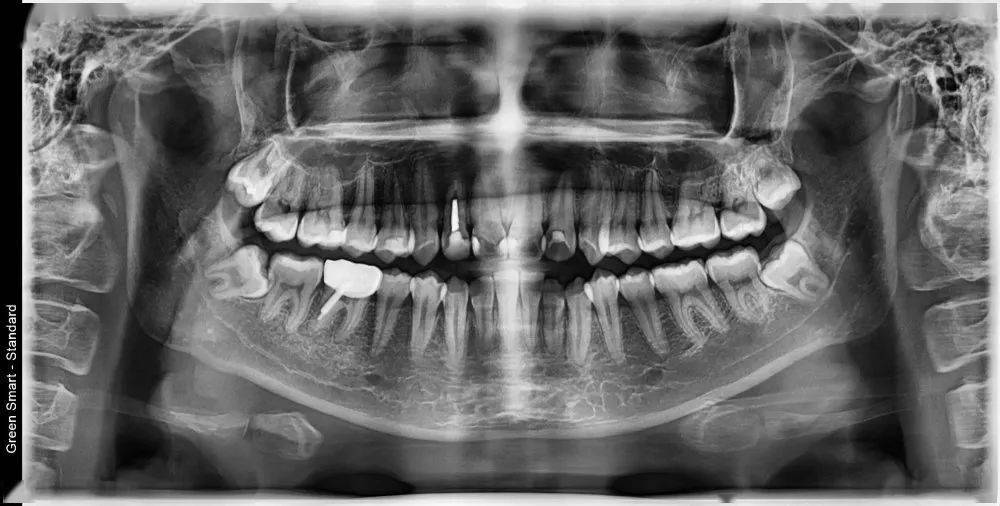

从挂号、拍片检查 , 会诊 , 取牙模

讨论矫正方案 , 整个过程一气呵成

经过主治医生的详细分析

发现牙齿的问题主要是前突不齐

颜面部左右不对称

口角高度不统一

四颗智齿都长歪了!!!

主治医师制订的矫治方案是

要拔八颗牙

(因为智齿阻生 , 建议四颗都拔掉)